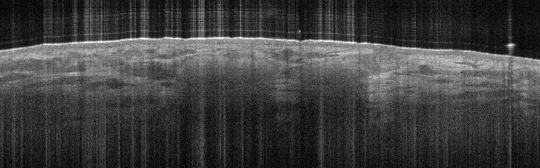

VA109: Left Dorsal Hand, Squamous Cell Carcinoma, Keratoacanthoma Type

- Note absence of collagenous texture in lower scan area